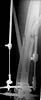

OK, we just fixed all fractures as the patient shows no infection signs. Posterior column was perQ (nice abbreviation) fixed by a screw and a wire, rami - by screws. Then closed locked nailing was performed (i placed a single screw at the upper level - is it commonly acceptable?) and "miss a nail" three cancellous screws to the neck (at the moment we have no more available implants suitable for this lesion like gamma nail etc, so the choice was easy :-). The external fixator left in place as a "local sceletal traction" for a couple of weeks. Acetabular, femoral shaft and neck images attached.